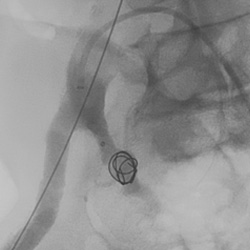

Peripheral embolization